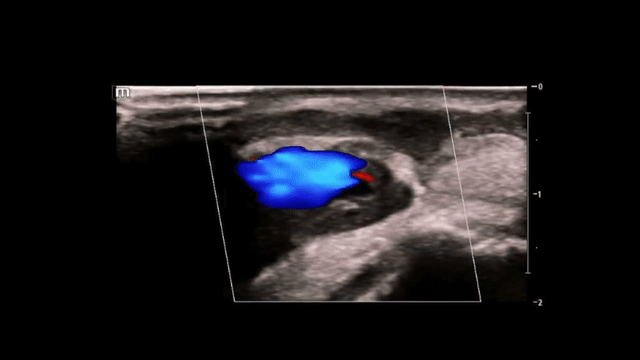

(Long-axis views of the right wrist with color doppler, bottom image shows the classic “yin-yang” sign which will be discussed below)

• “Yin-Yang” sign (turbulent bidirectional blood flow)

Here is a classic image of the characteristic “yin-yang” sign: